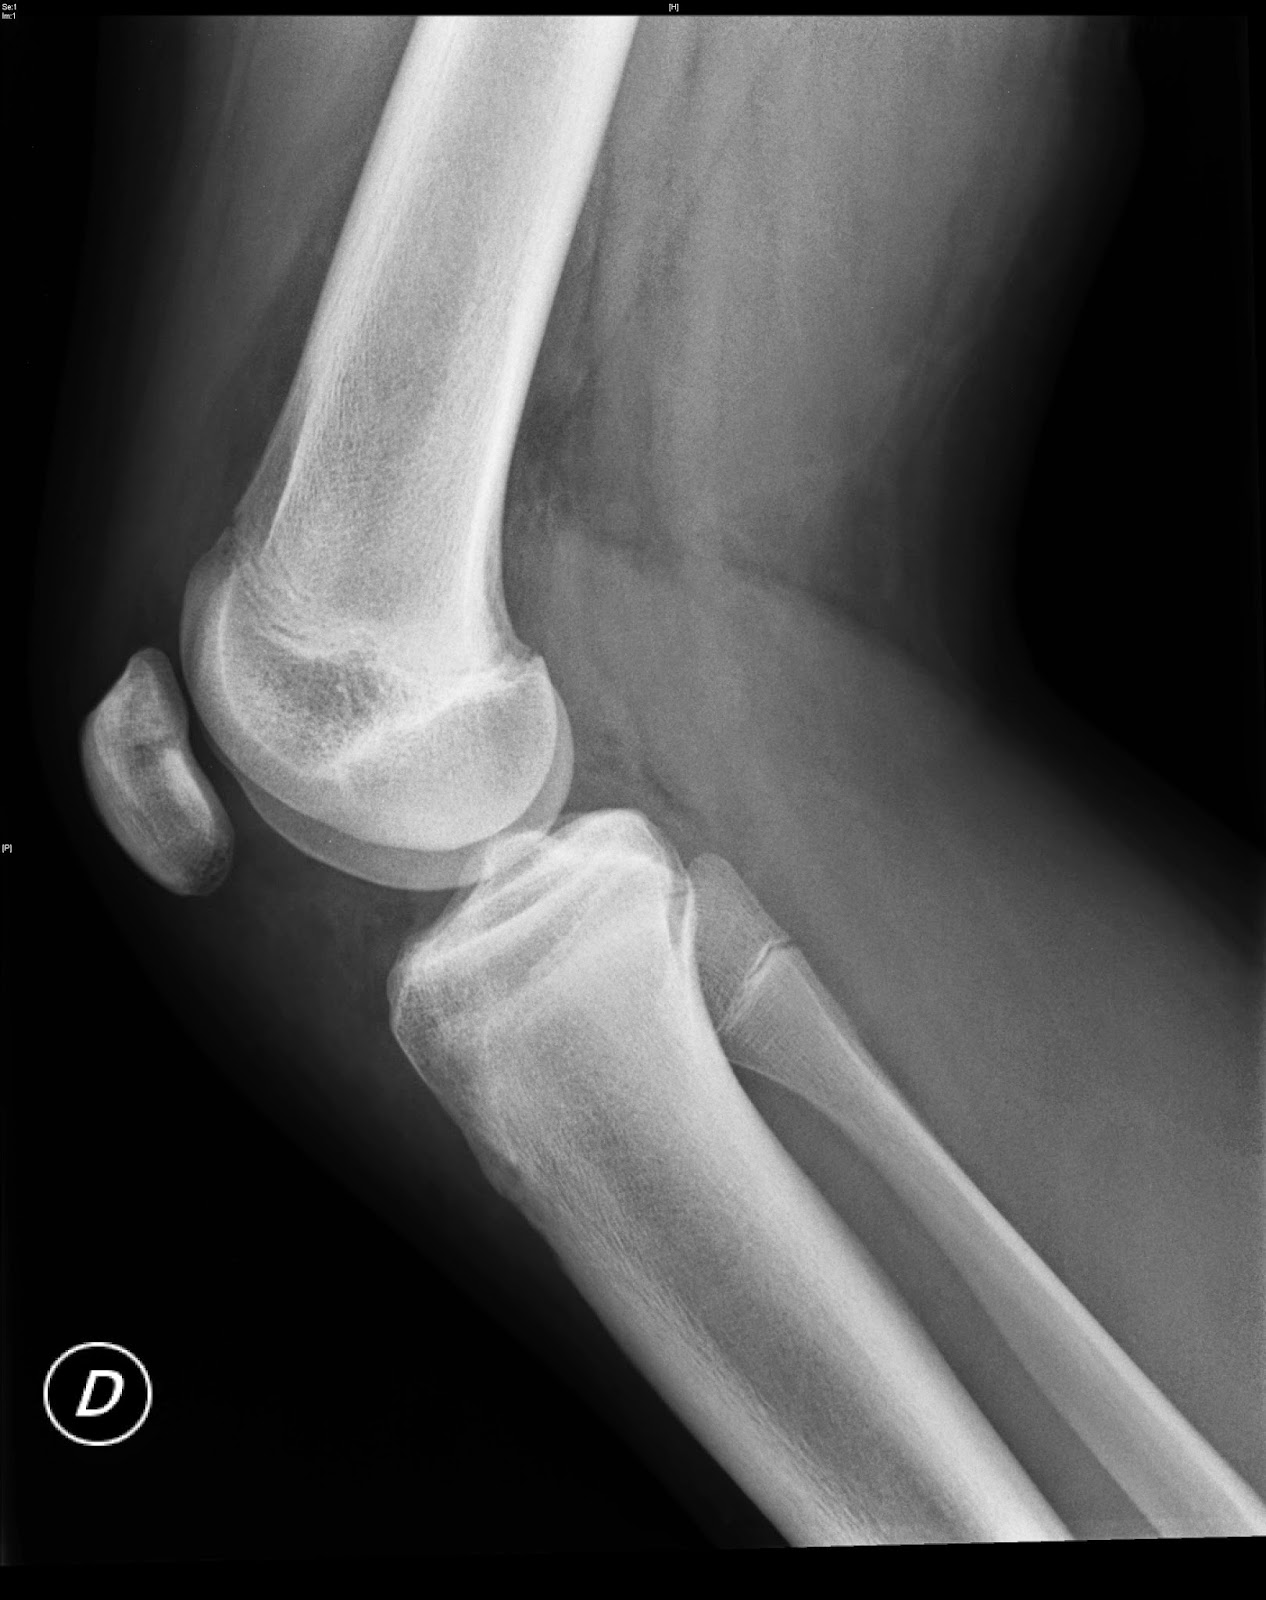

From continuum.aeped.es

Continuum Hallazgo radiológico inesperado tras un traumatismo de rodilla Aligned Rotula Rotula was associated to four peptides. This view demonstrates the distal femur and proximal tibia/fibula in their natural anatomical position allowing for assessment of suspected dislocations,. To examine molecular subdivision in the marine diatom thalassiosira rotula, variations in rdna sequence, genome size, and. The ‘secologanin synthase (sls)’ annotation in the transcriptome of t. To examine molecular subdivision in the marine. Aligned Rotula.

From docenciaaltopalancia.blogspot.com

Docencia Alto Palancia Rótula Bipartita.IMAGEN DOCENTE. Aligned Rotula Here we studied the expression pattern of the pg biosynthetic pathway during different growth phases of the centric diatom. The ‘secologanin synthase (sls)’ annotation in the transcriptome of t. The ‘secologanin synthase (sls)’ annotation in the transcriptome of t. This view demonstrates the distal femur and proximal tibia/fibula in their natural anatomical position allowing for assessment of suspected dislocations,. To. Aligned Rotula.